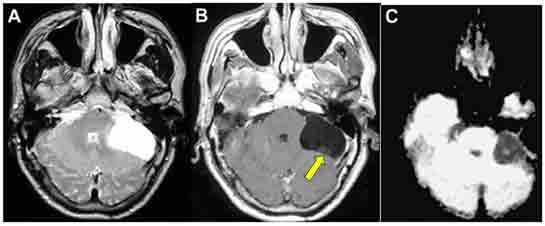

Beyinde kist tanısı genellikle görüntüleme yöntemleri kullanılarak konulur. Bu yöntemler arasında en yaygın olanları şunlardır:

• Manyetik Rezonans Görüntüleme (MRG): Beyindeki kistlerin detaylı bir şekilde görüntülenmesini sağlar.

• Bilgisayarlı Tomografi (BT): Kistin boyutu ve konumunu değerlendirmek için kullanılabilir.